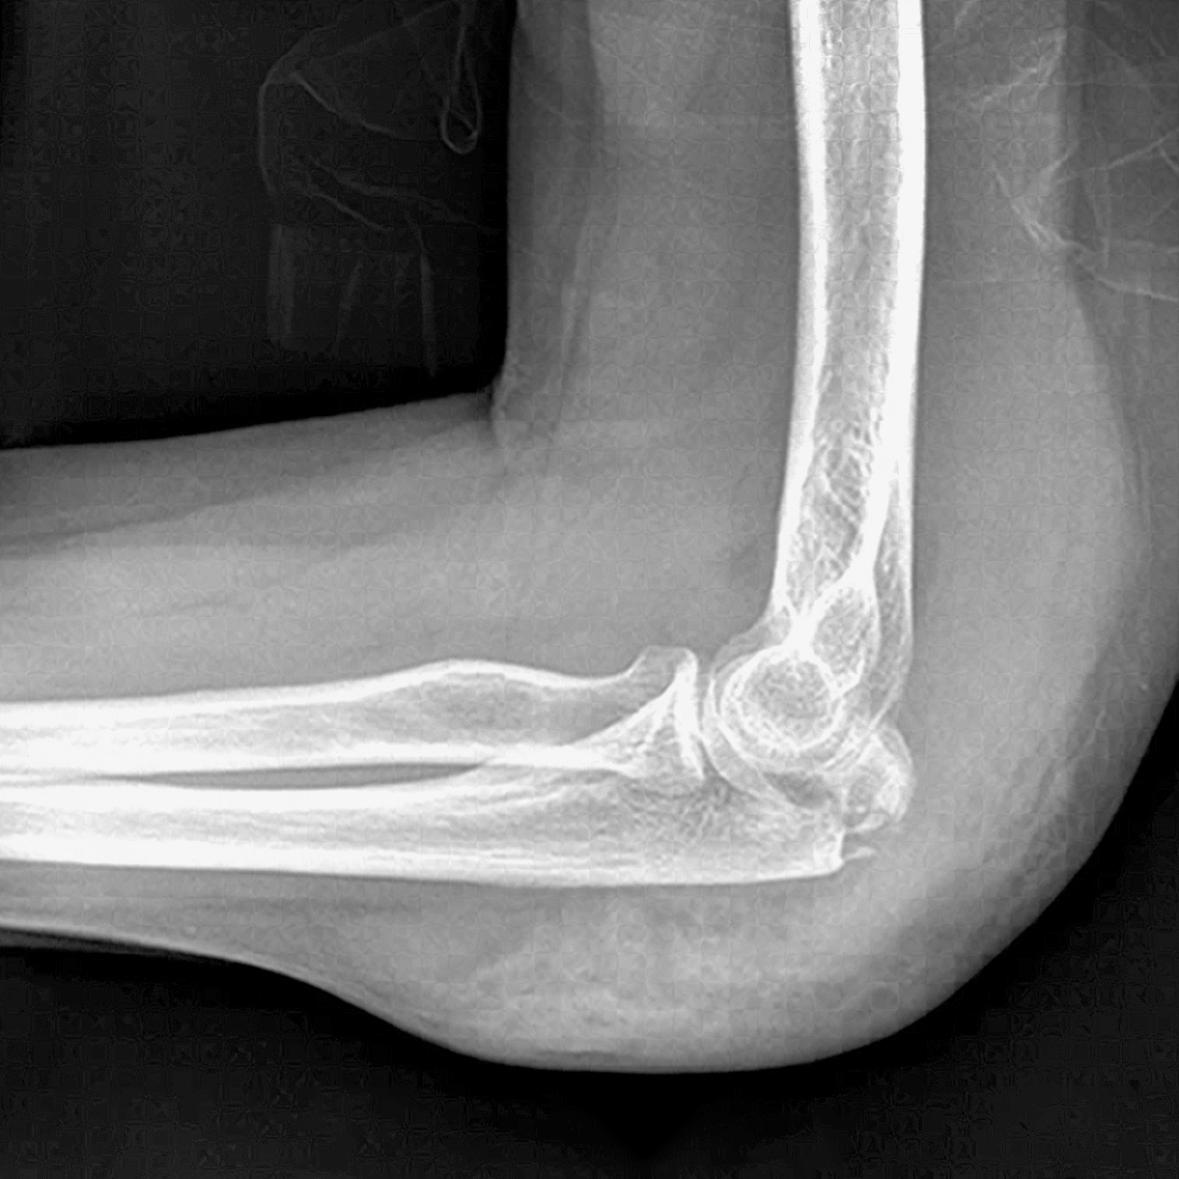

CLINICAL CASES: LEPORELLO CASE 2

We present a case of a comminuted, intraarticular fracture of the olecranon (AO 2U1C). The fracture was treated with the Bonebridge LEPORELLO 3.5mm Olecranon Plate.